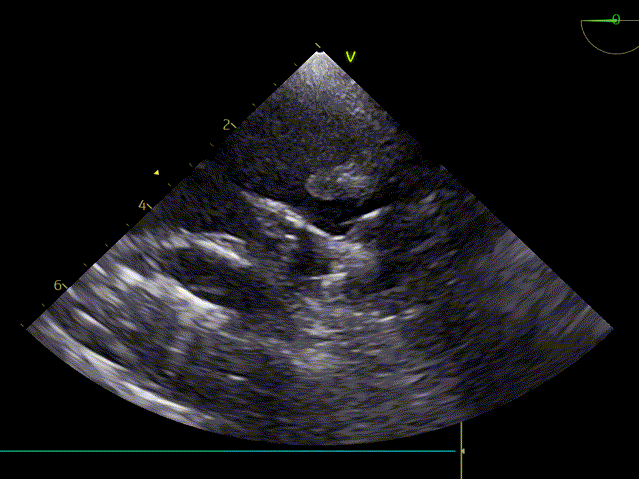

术前超声心动图:

主动脉瓣狭窄(重度,跨瓣平均压差69mmHg),房颤、心衰,反复住院2年;瓣环直径2.4cm,AV 5.0m/s EF 59%。